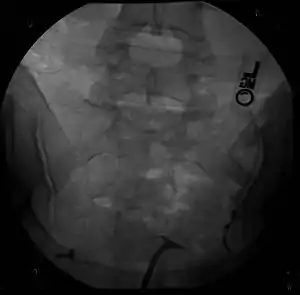

| A human bicornuate uterus | |